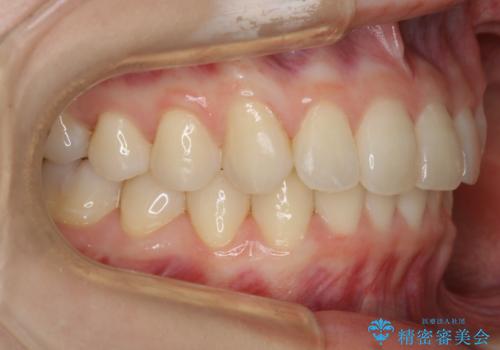

- 笑った時の歯の見え方を治したいとのことで矯正相談にいらっしゃいました。

一見そこまで大きなガタつきはないようにも見えますが、前歯の角度の不揃いや噛み合わせのズレなどから見え方に影響が出てしまっていました。

抜歯は全く必要のないレベルのガタつきだったため、マイクロインプラントを用いて歯全体を後方に移動させていくことできれいな歯並びを獲得することができました。